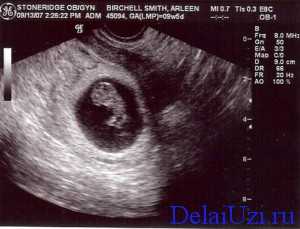

По показаниям проверяется количество прогестерона, низкое значение может спровоцировать прерывание беременности. На 9 неделе можно пройти УЗИ, если женщина не сделала его ранее. При выполнении ультразвуковой диагностики видны сердцебиение малыша, его движения. Исследование помогает оценить состояние эмбриона и матки, выявить патологии развития, определить замершую беременность.

Ультразвук на сроке в 9 недель проводится редко, чаще всего, если есть подозрение на замирание, патологии репродуктивных органов матери или если нужно узнать точный срок беременности. Получив данные по результатам УЗД врач может определить дальнейшую тактику ведения беременности и откорректировать ее. При обнаружении патологий плода обязательно проводится медикаментозное лечение.

Что могут показать результаты?

Важными событиями в развитии плода, которые можно увидеть на УЗД в том числе являются:

- Атрофирование эмбрионального хвоста.

- Размеры малыша уже в пределах 1,3-1,6 см, если делать замер копчико-теменного размера.

- У него уже сформированы пальчики на ручках и ножках.

- Происходит формирование костных тканей и мышц.

- Растет и развивается плацента и пуповина. На ультразвуке обязательно оценивают состояние этих важных параметров развития беременности.

Теперь ребенок может реагировать на раздражители мира, который окружает его маму. Так во время проведения УЗД, когда осуществляется незначительно надавливание на стенку живота или введение во влагалище датчика он начинает активные движения.

На этом сроке сердце – уже почти сформированный орган, число ударов за минуту около 180. Если необходимо уточнит количество сокращений мышцы, то назначают проведение допплерометрии.

Лицо уже почти как у настоящего человека, можно увидеть ушные раковины. Развиваются внутренние органы, которые, конечно же, пока слишком малы для проведения их исследования. Причем рост органов настолько интенсивный, что они могут выпячиваться – не стоит волноваться на этом сроке – это нормально. Они станут на свои места только к концу первого триместра.

Важное событие это недели – формирование мозжечка и гипофиза. Первый отвечает за координацию движения, второй за продуцирование гормонов. Уже происходит закладка надпочечников, они будут главными при выработке адреналина. Также формируются лимфоузлы, молочные железы, половые органы. О поле ребенка говорить еще рано, он еще слишком мал, чтобы можно было что-то рассмотреть.

В ходе УЗД в 9 недель, если оно назначается, происходит мониторинг состояния матки и ее придатков. Важным событием является начало регресса желтого тела, ведь плацента уже практически перебрала на себя его функции. Еще может просматриваться желточный мешочек, ведь он пока что выполняет функцию кровотворения.

Ваш будущий ребенок сейчас официально будет именовоться вплоть до родов не эмбрионом, а плодом. Его маленький эмбриональный хвостик исчез. На УЗИ плода в 9 недель беременности размеры соответствуют средней оливке, это 14-15 мм, а у плода ужеимеются крохотные ручки и ножки, пальцы на которых все еще перепончатые. Начинают формирование кости и сухожилия. Пуповина и плацента формируются и растут, на УЗИ плода в 9 недель беременности измеряется толщина хориона (плаценты), определяется пуповина. Плод способен отвечать движениями на прикосновения к передней брюшной стенке в проекции матки, например при проведении УЗИ при беременности. Сердце плода становиться достаточно большим и практически сформированным, частота сердечных сокращений достигает 180 в этот период, что можно отметить при УЗИ плода в 9 недель беременности с применением допплера. Лицо плода становится более сформированным, уши более выступающими, продолжают совершенствоваться печень, селезенка и желчный пузырь. Конечно, все эти органы еще невозможно увидеть на УЗИ плода в 9 недель беременности, это будет возможно несколько позже. Внутренние органы плода в девять недель беременности еще могут выпячиваться в виде пупочной грыжи.Это можно увидеть на УЗИ плода в 9 недель беременности и это нормально для данной стадии развития. Полное возвращение внутренних органов в пределы передней брюшной стенки плода в норме происходит после 10 недель беременности. При УЗИ плода в девять недель беременности обязательно оцениваются яичники. Желтое тело при УЗИ яичников начинает свое обратное развитие, так как формируется полноценная плацента, способная взять на себя полностью гормональную поддержку развивающейся беременности. Желточный мешок пока все еще визуализируется, он еще не выполнил свою основную кроветворную функцию. Иногда его можно даже увидеть при УЗИ плода в 12 недель беременности.